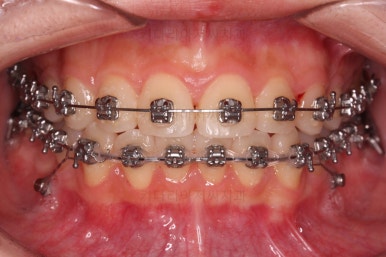

기타 부위들의 디테일을 좀 더 맞춰주고 부산교정 치료를 종료합니다.

전후사진을 비교해 볼게요.

약간의 주걱턱, 돌출입은 고칠 의사가 없어서 그대로 유지하였고 주걱턱 패턴으로 인한 부정교합 부분을 개선했으며 무엇보다 중요한 것은 쓰러져서 많이 썩어있던 치아를 자칫 치료 못할 뻔 했는데 교정치료와 병행하여 훌륭하게 치료를 하여 살려 썼다는 점입니다.

그리고 사랑니 발치 + 충치치료 + 교정치료 모든 것이 키다리아저씨치과 한 곳에서 다 가능하다는 점이 치과의 매우 큰 장점이지요.